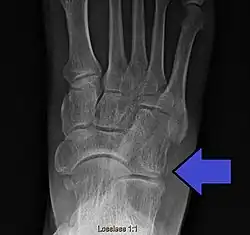

Avulsion fracture of the right cuboid bone of the foot